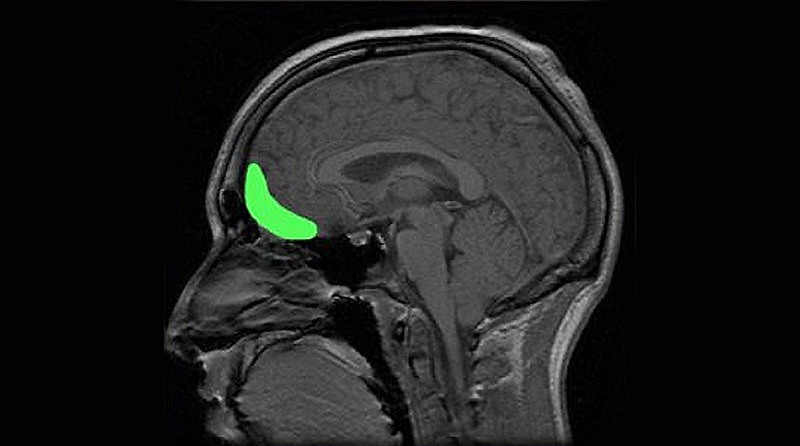

Ученые обнаружили, что за положительные мысли и мечты отвечает передний участок среднего мозга — область орбитофронтальной коры (Orbitofrontal Cortex, OFC). Орбитофронтальная кора расположена в префронтальной коре сразу за человеческими глазами. Давно известно, что она играет определенную роль в тревожных расстройствах, в эмоциональной и поведенческой регуляции путем интеграции интеллектуальной и эмоциональной информации. Размер орбитофронтальной коры, по-видимому, связан со склонностью к тревоге или к оптимизму. Область находится позади глаз и активизируется, когда люди начинают думать о хорошем будущем. У более оптимистично настроенных людей активизация проходит в более ярко выраженной форме.

из Университетского Колледжа в Лондоне. Орбитофронтальная кора головного мозга